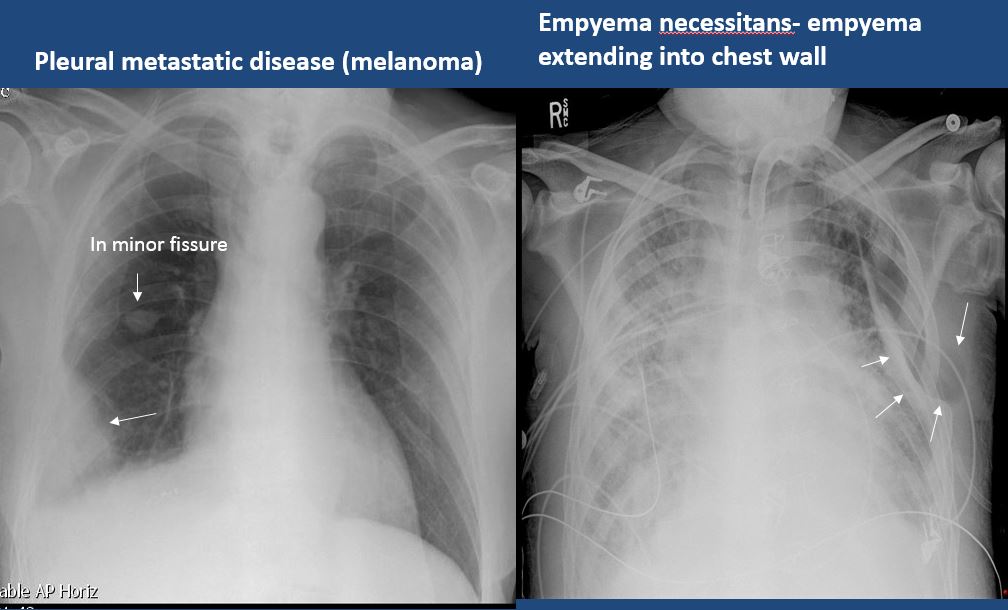

There is focal or diffuse abnormality of the pleura or chest wall. [Yes/No]

There is focal fluid in the fissures. [Yes/No]